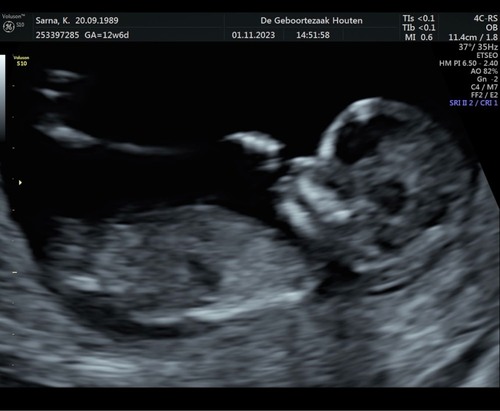

Hoihoi, dit heb ik laten doen, gewoon uit nieuwsgierigheid. Ik heb nog een foto, kan iemand zien of dit een beetje klopt ?

Deze